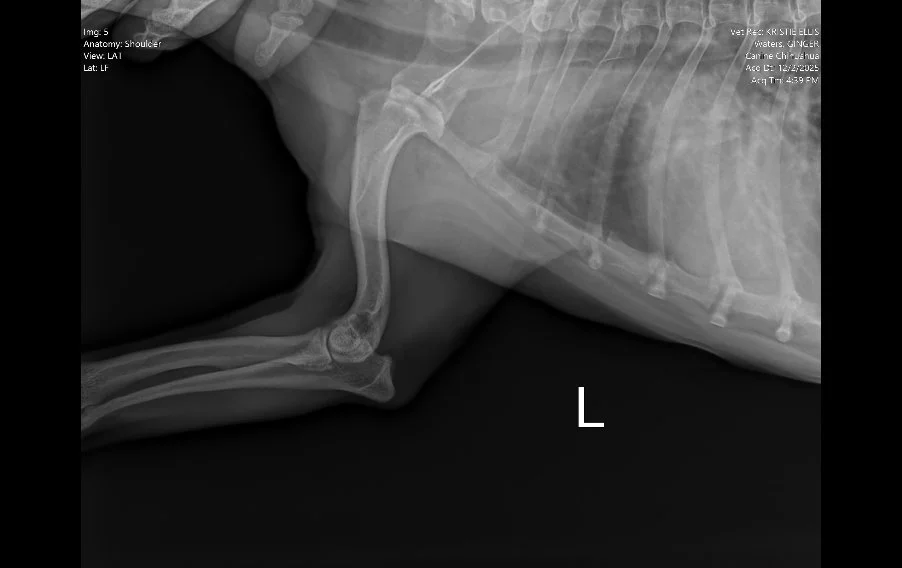

Lateral shoulder radiograph in a dog showing decreased joint space consistent with mild arthritis

Image 4. Lateral radiograph of the left shoulder.

Radiographs (Images 1–4) of the left forelimb, including the carpus, elbow, and shoulder identified:

• Mild degenerative joint disease (arthritis)

• Decreased shoulder joint space

• No fractures, masses, or bone lysis

Based on these findings, Ginger was treated for osteoarthritis. However, her clinical progression did not match the imaging results.